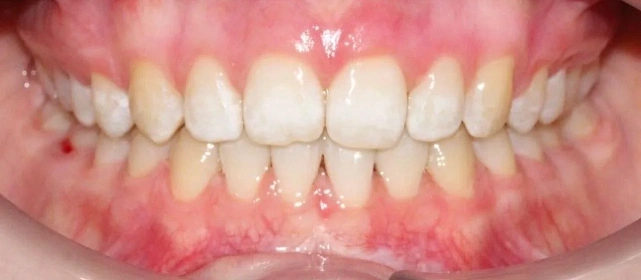

Скученность зубов, обе челюсти сужены — зубам не хватало места в ряду.

Проблема: Пациентка обратилась с одной жалобой — неровные зубы. При осмотре обнаружили, что обе челюсти сужены, зубам банально не хватает места, отсюда скученность. Зубы здоровые, ортопедия не нужна — чисто ортодонтический случай.

Решение: Установили брекеты на обе челюсти. Расширили дуги, убрали скученность — всё за 15 месяцев. Визиты раз в 4–6 недель для замены дуг. После снятия зафиксировали ретейнеры на обе челюсти, сняли сканы для кап. Ортопед подтвердил, что протезирование не требуется. Терапевт рекомендовал лечение — пациентка записана.

Скученность на обеих челюстях при сужении дуг — классический случай. Зубы здоровые, корни в хорошем состоянии, мотивация у пациентки высокая. Всё это позволило уложиться в 15 месяцев без осложнений. Ортопед подтвердил, что протезирование не нужно. Рекомендовала пройти терапевтическое лечение для полного завершени